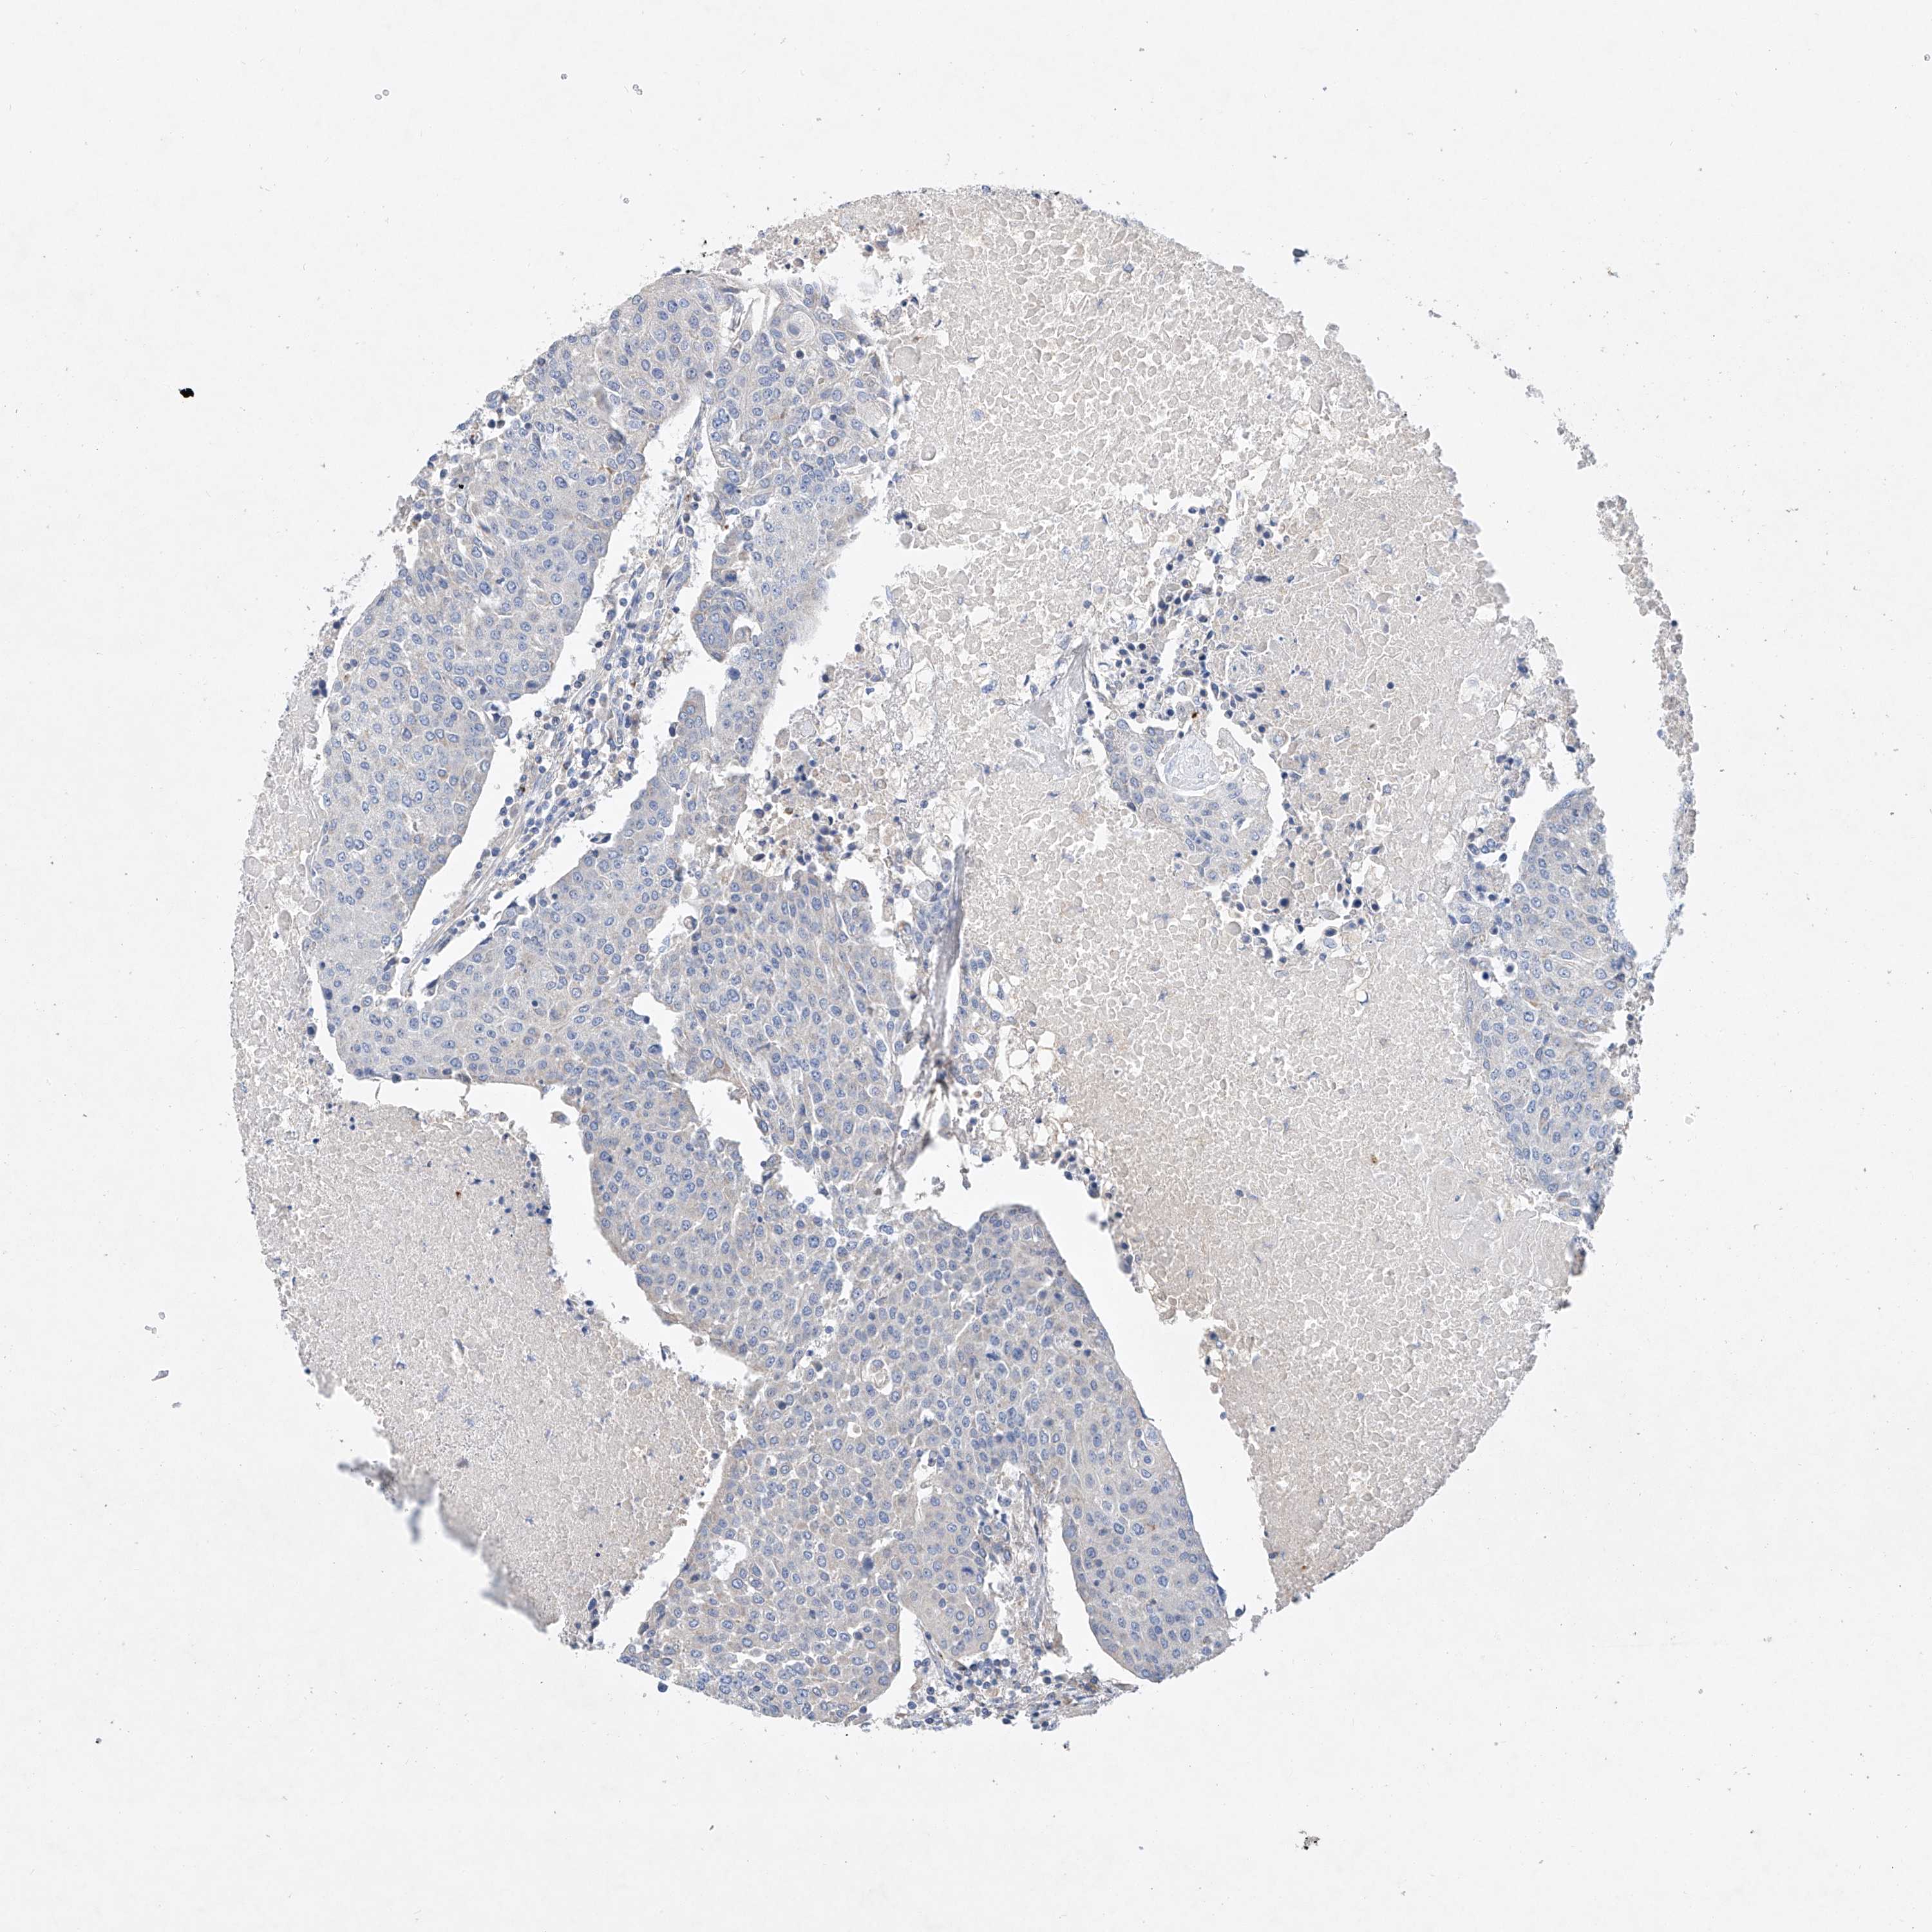

UROTHELIAL CANCER - Protein expressioni

A mouse-over function shows sample information and annotation data. Click on an image to view it in a full screen mode. Samples can be filtered based on level of antibody staining by selecting one or several of the following categories: high, medium, low and not detected. The assay and annotation is described here.

Note that samples used for immunohistochemistry by the Human Protein Atlas do not correspond to samples in the TCGA dataset.

Antibody stainingi

Antibody staining in the annotated cell types in the current human tissue is reported as not detected, low, medium, or high, based on conventional immunohistochemistry profiling in selected tissues. This score is based on the combination of the staining intensity and fraction of stained cells.

Each image is clickable and will lead to virtual microscopy that enables deeper exploration of all samples and also displays staining intensity scores, fraction scores and subcellular localization as well as patient and tissue information for each sample.

Antibody HPA029281

Antibody HPA029282

Urothelial carcinoma, High grade